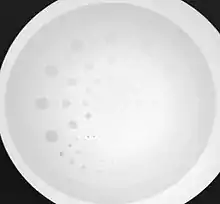

Fig. 6.20: An image of a contrast-detail test phantom acquired using a fluoroscopy system.

• Contrast-detail evaluation combines physical indices of image quality with observer detection ability. Contrast-detail phantoms contain test objects of different sizes and subject contrast mounted on a plastic plate that is radiographed under specific exposure conditions - see Figure 6.20. Contrast-detail plots are derived on the basis of the borderline visibility of test objects in the image. A disadvantage of this approach however is the introduction of bias as a result of the observer's prior knowledge of the size, shape and location of the low-contrast objects. The link between this type of evaluation and clinical imaging performance is therefore difficult to establish.